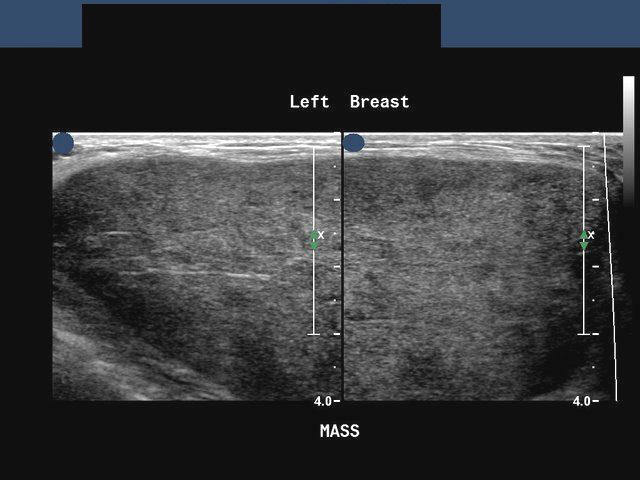

Carcinoma breast -case-4

Ultrasound images of malignant mass left breast